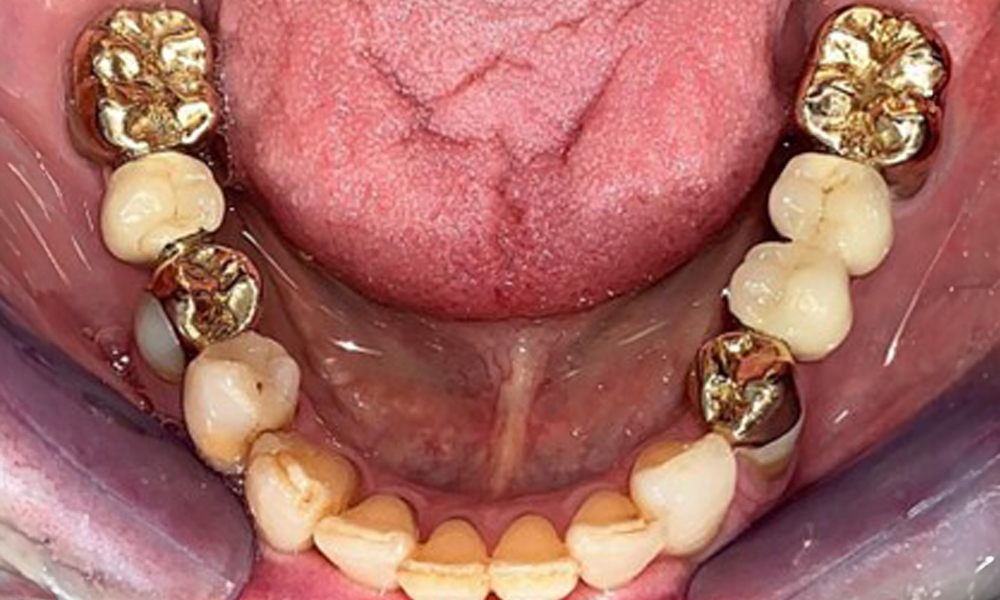

The patient was fitted with a combined removable maxillary telescopic prosthesis more than 25 years ago (Fig. 1, Fig. 2, Fig. 3) and is very happy with her dentures. The patient has an adequate fixed denture for the mandible (Fig. 4).

Occlusal view of the mandible.

Fig. 4: Occlusal view of the mandible.